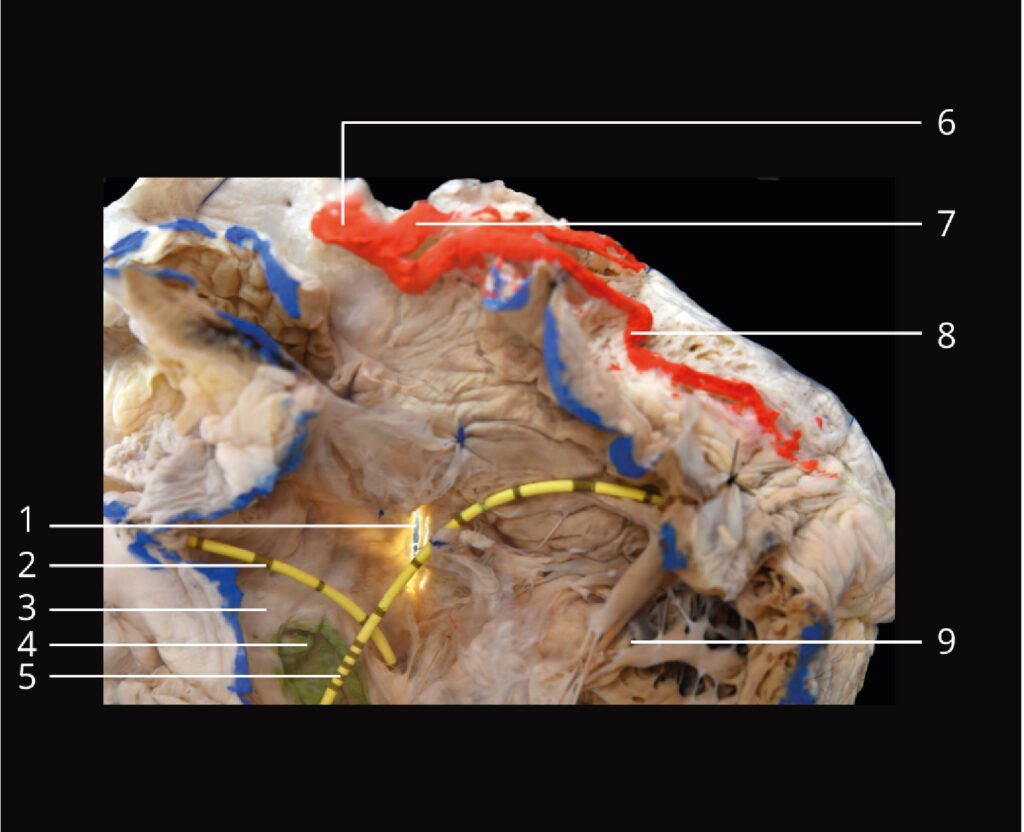

Museo.

Encontrarás los preparados de nuestro laboratorio en el museo de Anatomía J. J. Naón, Facultad de Medicina, Universidad de Buenos Aires, con su descripción.

Encontrarás los preparados de nuestro laboratorio en el museo de Anatomía J. J. Naón, Facultad de Medicina, Universidad de Buenos Aires, con su descripción.